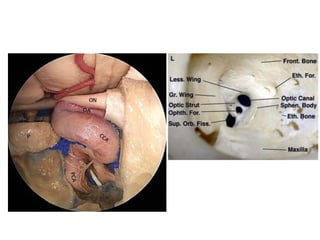

anterior ethmoidal artery ( AEA) and nerve

Accessories

Orbit